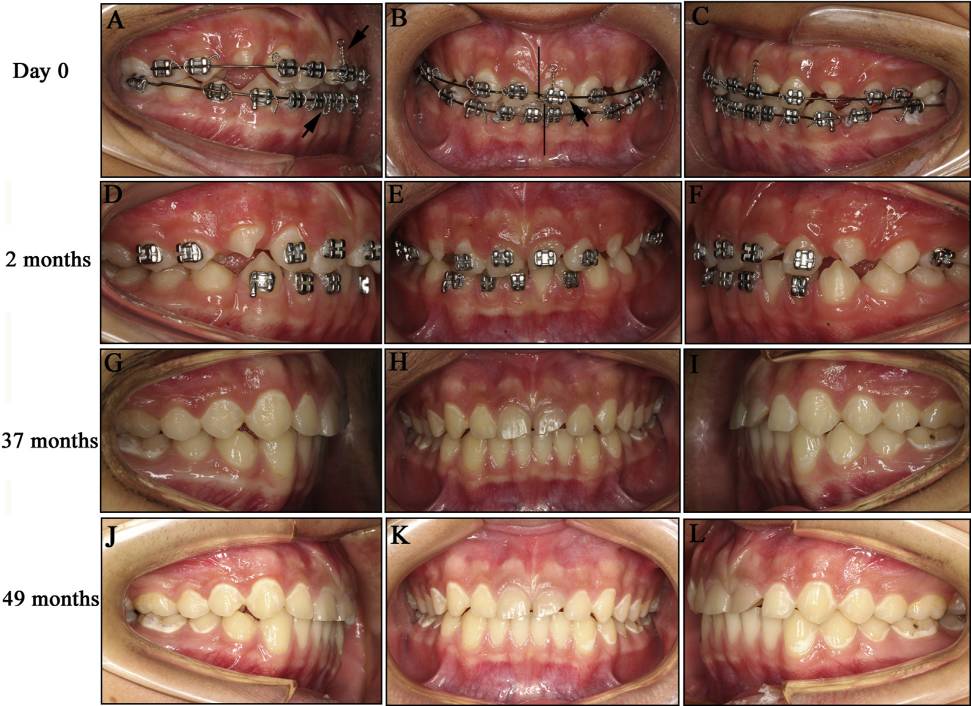

Fig 2. 放置正畸托槽后的口内照片: A-C, 0天; D-F, 2个月; G-I,37个月; and J-L, 49个月。结扎丝被弯曲以供橡皮圈插入 (A图箭头).两侧上颌中切牙都折断了:右侧中切牙向近中侧折断,左侧中切牙失去了三分之一 ( B箭头) 上颌牙齿中线与面中线一致,下颌牙齿中线偏移2mm(B的竖线表示上下颌牙列中线)。治疗后两个月(D-F), 牙列中线一致(E)。在治疗后第37和49个月,牙列中线依然保持一致,咬合维持稳定 (G-L)

接下来的随访分别在第一次随访后的第1,2,20,37和49个月。在第一个月随访之后,牙齿和面部中线已经一致,面部重新达到对称。医生指示患者停止使用橡皮圈,同时取下上下牙弓的弓丝。但是托槽要继续留在牙齿上,以备后续使用之需。患者被建议进食粥和软米饭,并进行小范围的开口和闭口练习。在第二个月的复诊中(Fig 2, D-F),取下托槽,不进行更多的治疗。此时,已经可以观察到临床恢复。

对比第2,37和第49个月拍摄的面部和口内照片可以发现,面部对称性保持良好,没有中线偏移(Fig 2, E, H, and K)。右侧髁突已经显示出重建完成的影像学表现,左侧髁突在髁头部显示有轻微弯曲,这是不完全重建的表现(Fig 3, E)。下颌骨正中联合处的骨折已经痊愈。